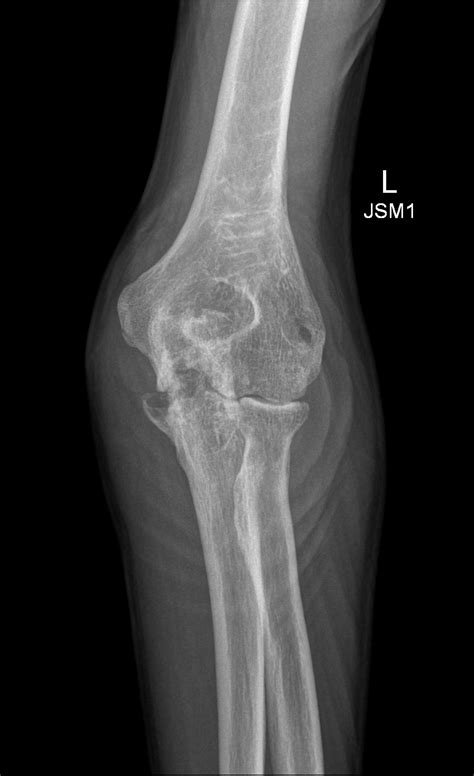

To determine if you have a bone spur elbow, a healthcare professional will typically conduct a physical examination followed by imaging studies. During the physical exam, they will test your range of motion and look for areas of tenderness. Imaging is essential to confirm the diagnosis and assess the extent of the growth.

X-Ray The most common method to visualize bone density and identify bony projections.

CT Scan Offers a more precise 3D view of the bone structure if the X-ray is inconclusive.